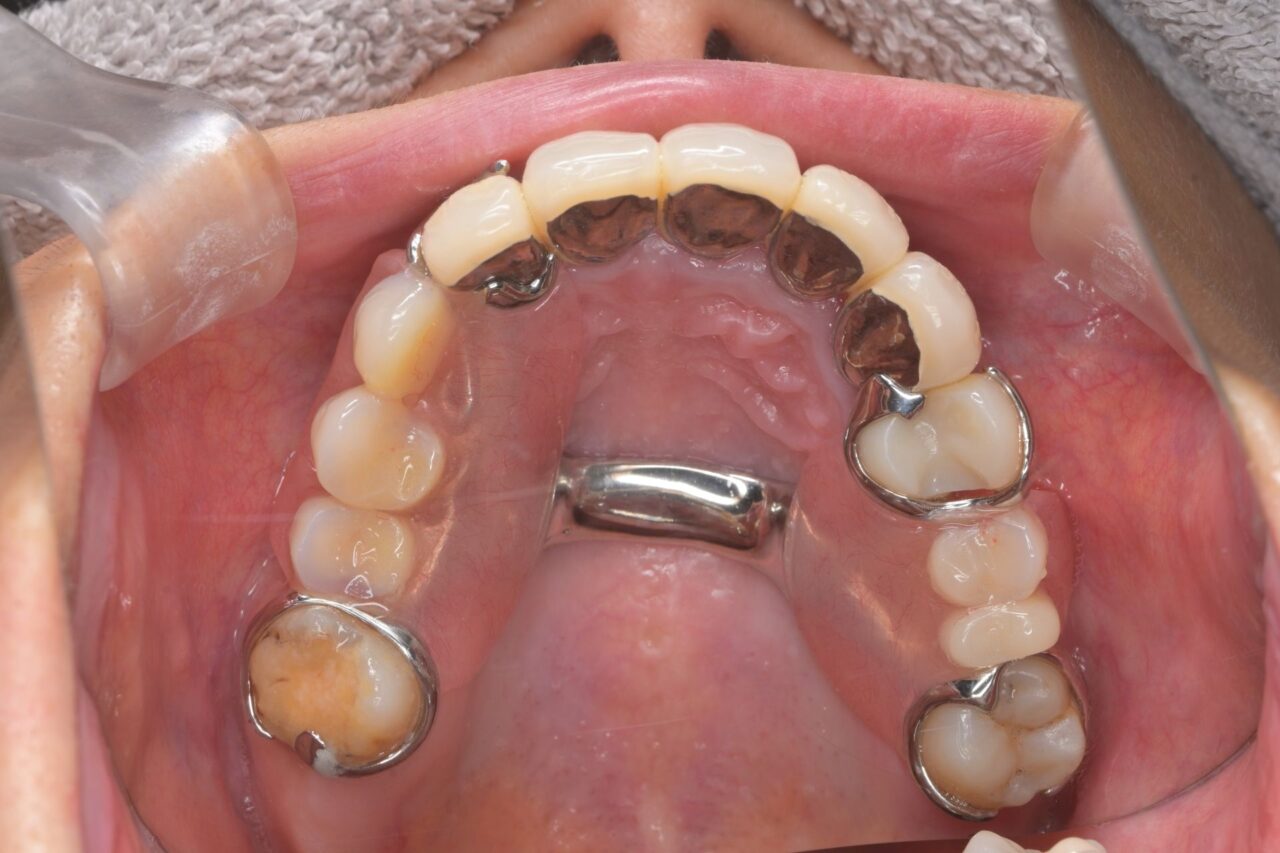

上面

大きな虫歯が放置されていた入り、かぶせ物が無くなって放置されていたり、様々な問題があります。保険治療で済ませようと思うと入れ歯は確定です。

歯が無い部分は入れ歯で補いました。

左右の入れ歯を金属でつないで強固にしています。はじめは舌感が悪いと思いますが、慣れが必要です。